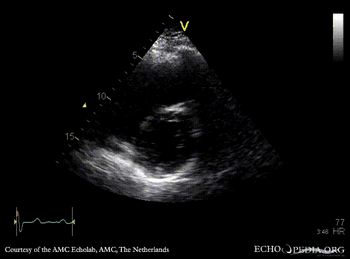

E00310.gif E00311.gif

Subcostal view: ASD type II TEE: ASD type II